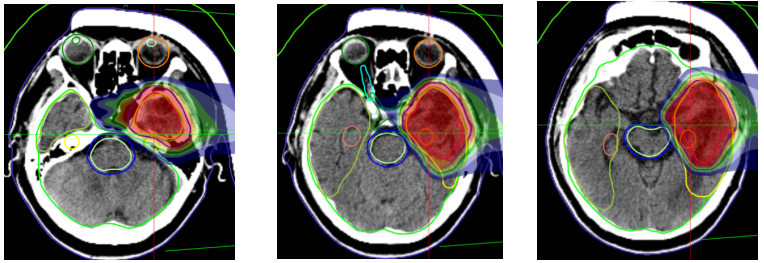

Figure 6: The prescribed dose for the left frontotemporal lobe mass is 45 Gy (RBE) in 15 fractions.

Figure 7: Treatment plan: Prescription dose: The PTVm prescription dose is 60 Gy (RBE) in 20 fractions.